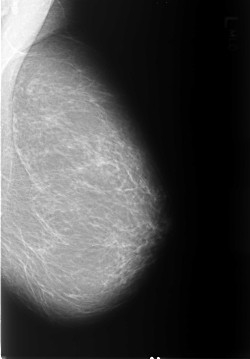

B_3228_1.LEFT_CC

LEFT_CC LINES 5464 PIXELS_PER_LINE 4016 BITS_PER_PIXEL 12 RESOLUTION 50 NON_OVERLAY

FILE: B_3228_1.RIGHT_CC.OVERLAY

TOTAL_ABNORMALITIES 1

ABNORMALITY 1

LESION_TYPE MASS SHAPE ASYMMETRIC_BREAST_TISSUE MARGINS N/A

ASSESSMENT 2

SUBTLETY 4

PATHOLOGY BENIGN_WITHOUT_CALLBACK

TOTAL_OUTLINES 1

BOUNDARY